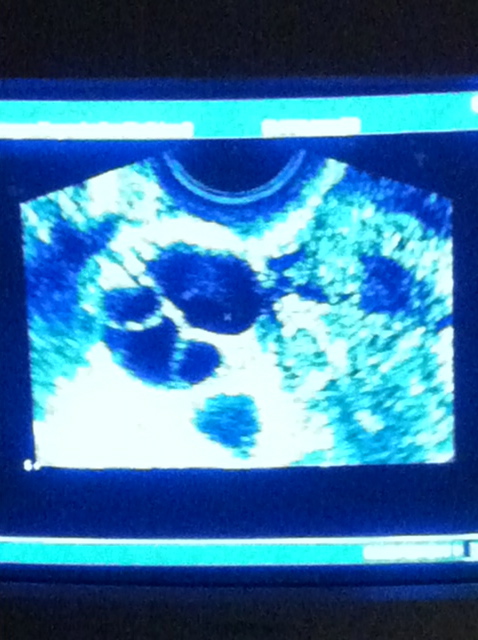

So, here are the final stats on my follicles and blood work.

– I showed 20 follicles today! Yowza! BUT…

– About 10 of those were too big or too small to assume they’ll be “viable” (one was at 28 mm, no wonder it’s uncomfortable to walk at this point!)

– About 10 look like they are “just right” and will likely be fertilized. Yah!

– My estrogen is over 3000 today- and I feel it. Seriously. It’s like having way too many drugs in my body and everything is just, too much.

– He said that my follicles are “much farther apart in size than what’s average”. You have to get that Dr. H rarely uses words like “much farther” followed by “average”- he’s just not a dramatic kind of guy…nor does he like to alarm us overly estrogenated women. But, for me, I had eggs that were 7mm to 28 mm, and he likes the follicles to all be right around 18mm at this stage. Again, I never was one to confirm so I guess my follicles are not either.

– Suffice to say, he still is “very pleased” and when I asked him if we’ll lose the largest follicles and he told me that’s likely, “but,” he reminded me, “there is nothing to worry about.” So, I will not worry. He’s happy. I’ll be happy. All part of my game called surrender. While my health and my body are mine, I am also learning to give way to the expert who really knows how to get a girl knocked up. And so it goes.